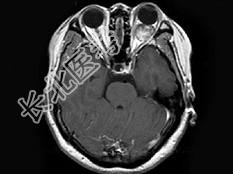

- 单项选择题女,47岁, 左眼球突出伴视力下降半年,MRI平扫及增强扫描见眶内占位性病变, 最可能的诊断是 ( )